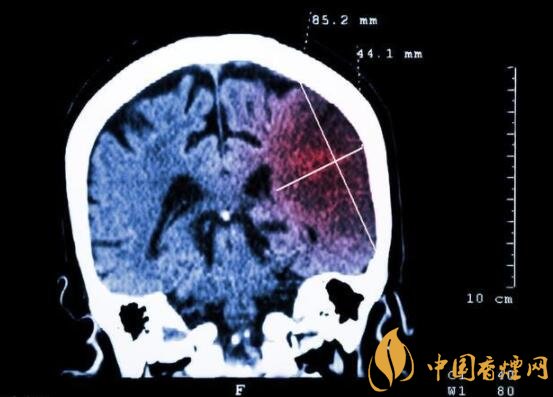

一般而言,急性腦梗塞與長(zhǎng)期吸煙有非常密切的聯(lián)系。有長(zhǎng)期煙齡遇到肢體活動(dòng)不順,做頭顱核磁共振檢查往往查出一側(cè)大腦中動(dòng)脈閉塞的可能性很高。由此可見,吸煙確實(shí)與中風(fēng)存在一定聯(lián)系。